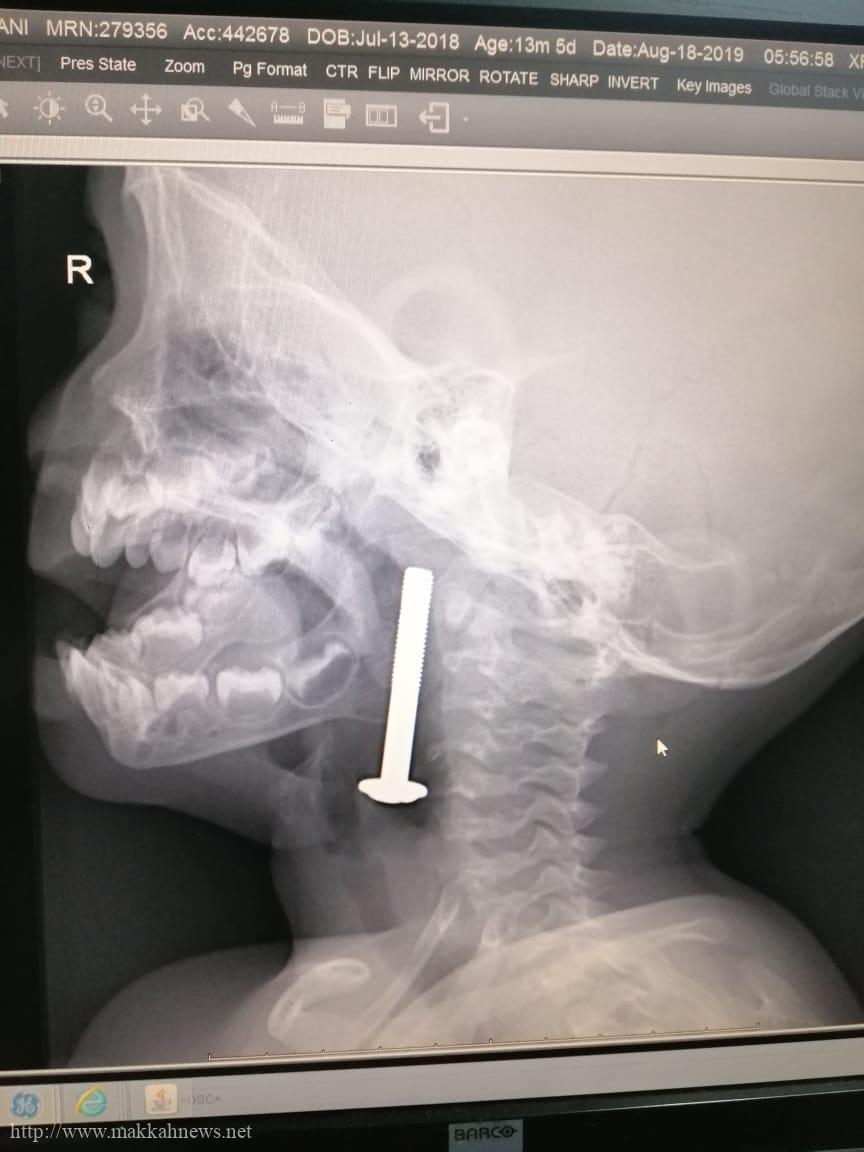

جراحة ناجحة لإنقاذ حياة طفل إبتلع مسمار حديدي بمكة

(مكة) – فوزية الفواز أجرى فريق طبي بمستشفى النور التخصصي بمكة المكرمة عملية جراحية عاجلة لإنقاذ حياة طفل عمره سنة…